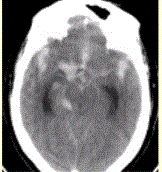

问题 患者男,50岁,突发昏迷、呕吐1h。查体:颈项强直,脑膜刺激征阳性,CT表现如图1。 进一步确诊蛛网膜下腔出血的病因,应首选

选项 A.CTA B.MRA C.MRI D.MRI增强 E.CT增强

答案 A